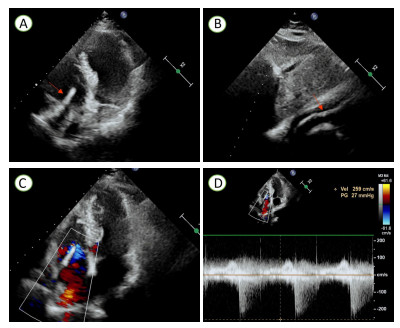

1 病例资料患者,女,71岁,因“检查发现右室异物2 d”入院。患者1个月余前因骨质疏松伴腰2椎体病理性骨折,行经皮椎体成形术。近日拟再次行骨科手术,术前检查发现右心腔内强回声。为进一步手术治疗入院。查体:心率118次/min,血压141/100 mmHg(1 mmHg=0.133 kPa),心前区无隆起,心界向两侧扩大,心律齐,瓣膜听诊区未闻及明显杂音,余正常。辅助检查:心电图检查示:正常心电图。经胸超声心动图检查示:右房室腔内可见一长条状高回声,可见段长约75 mm×5 mm(图 1A~B),不活动,三尖瓣形态、回声及开放活动未见明显异常,右房侧可见少许反流束(图 1C),测三尖瓣口收缩期最大反流速度为2.59 m/s,估测无肺动脉高压(图 1D)。超声诊断:右心腔异常回声,结合临床考虑骨水泥;三尖瓣轻度反流。CT平扫检查示:两肺见条片状致密影,沿血管分支分布(图 2A~B)。心脏形态及大小未见明显异常,右心见条状致密影(图 2C);主动脉钙化;椎体术后改变(图 2D),提示:主动脉钙化。两肺致密影,疑似骨水泥肺栓塞,椎体术后。结合病史,初步诊断:心脏异物、心功能Ⅱ级、腰椎椎体成形术后、骨质疏松。

| 注:A为二维心脏超声(心尖四腔心切面)显示右房室腔内高回声(红色箭头处);B为二维心脏超声(剑突下切面)显示右房室腔内长条状高回声(红色箭头处);C为彩色多普勒超声显示三尖瓣反流信号;D为频谱多普勒显示三尖瓣口收缩期最大反流速度为2.59 m/s 图 1 患者术前经胸超声心动图图像 |